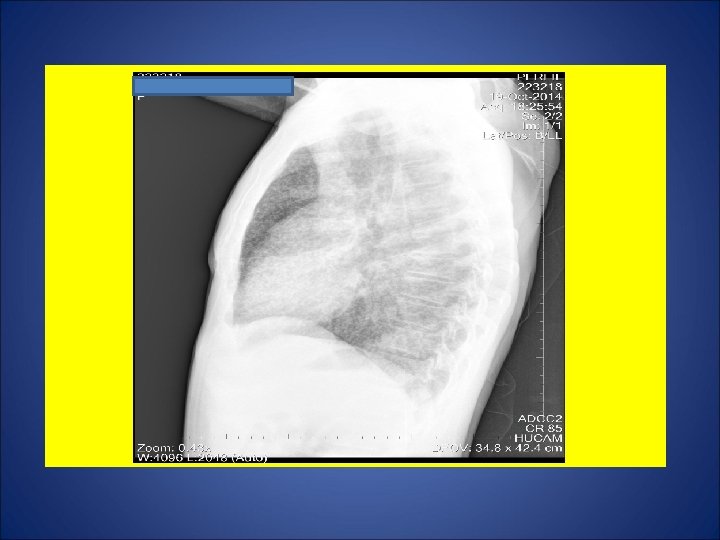

CASO 1: Paracoccidioidomicose em mucosa lingual diagnosticada por biópsia de lesão lingual em Fev/10, sendo iniciado STX-TMP 2 cp 12/12 h. Porém, fez uso irregular. Devido à não melhora clínica da lesão em queixo, o paciente foi internado em 09/out/14 para administração endovenosa de anfotericina B. Durante os últimos 2 -3 meses, relatou febre vespertina não aferida. Remissão da febre desde que internou. Tosse produtiva por 3 dias precedendo a sua internação em 09/out/14. Há mais ou menos 1 ano e meio, surgimento de lesão ulcerada em região inguinal direita próximo à bolsa escrotal. Regressão da lesão após introdução da anfotericina B. Lavrador (trabalhou em plantação de cana, milho, feno e carvoaria), mecânico (trabalhou em oficina de conserto de carro), pescador, servente de pedreiro. Negou contato com casos de tuberculose. Negou tuberculose prévia. Tabagista e etilista. HIV negativo. Ex. fisico: úlcera com várias crostas hemáticas em queixo acometendo o lábio inferior e as comissuras labiais, descorado (1+/4). Marca de BCG em MSD.

ESCARROS ESPONT NEOS: 1º) 20/10/14: 5 m. L – SALIVA – 1: 30 h: BAC NEG – TRM M. tuberculosis detectado - CULT em curso 2º) 21/10/14: 5 m. L – SALIVA – 30 min: BAC NEG – CULT em curso 3º) 22/10/14: 8 m. L – MUCÓIDE – 50 min: BAC NEG – CULT em curso